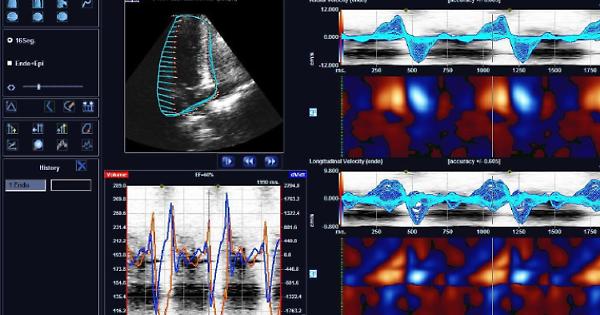

Anche a Venaria, nell’attuale ospedale di piazza dell’Annunziata - in attesa che il polo sanitario nuovo di corso Machiavelli sia completato - arriva una grande rivoluzione tecnologica: il “Sistema Integrato Ris Cvis Pacs”, strumento informatico sofisticato ed evoluto, per l’acquisizione, gestione, archiviazione e distribuzione digitale delle bio-immagini prodotte dalle aree di attività diagnostica radiologica, cardiologica, neurologica, gastroenterologica e ginecologica.

Il Ris è l’acronimo tradotto dall’inglese di “Sistema Informatico Radiologico” e ha il compito di assicurare la gestione complessiva del flusso di lavoro e dei dati nel reparto di Radiologia e nelle aree complementari alla Radiodiagnostica.

Il Pacs, invece è il “Sistema di archiviazione e trasmissione delle immagini” e ha la funzione di provvedere alla generazione, visualizzazione e distribuzione delle immagini, sia ai fini della refertazione sia dell’archiviazione.

Infine c’è il “Cvis Pacs”, che è dedicato alla gestione delle informazioni e delle immagini prodotte da diverse specialità cardiologiche (elettrocardiografia, ecocardiografia, elettrofisiologia, emodinamica).